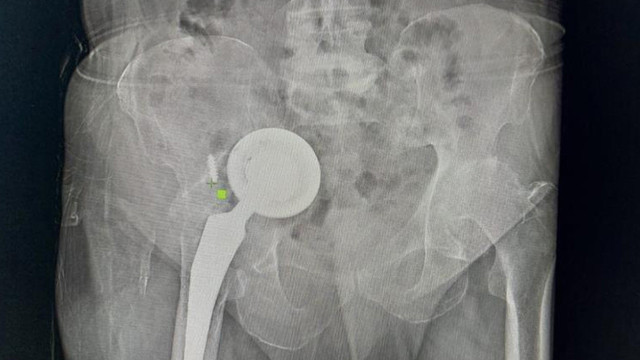

Yıllarca ağrılarından rahatsız olan 74 yaşındaki Ömer Demir, geçirdiği iki kalça protezi operasyonu sonrası doktorların gerekli bulmasına rağmen yeniden ameliyat olmak istemeyince kalçasındaki protez vücudunda hareket etmeye başladı. Protezin baş kısmı hastanın karnından, diğer parçası ise bacağından çıkarıldı.

Başakşehir Çam ve Sakura Şehir Hastanesi Ortopedi ve Travmatoloji Uzmanları Dr. Mustafa Özçamdallı ve Dr. Necati Doğan’ın ekipleriyle gerçekleştirdiği operasyonla protezin üst kısmı karın içinden alt kısmı ise hastanın bacağından çıkarıldı.

Protezin üst kısmının karın içinden alt kısmının ise bacaktan çıkarıldığını ifade eden Ortopedi ve Travmatoloji Uzmanı Dr. Mustafa Özçamdallı, “Hastamız bize geldiğinde yürüyemez bir vaziyetteydi daha önce birkaç kez operasyon geçirmiş ve protezi karın dediğimiz boşluğa kadar ulaşmış durumdaydı. Hastanın damarlarında ve sinirlerinde hasarlar meydana getirebilecek seviyedeydi. Özel dizayn edilmiş kafes dediğimiz protezlerle ve daha uzun revizyon dediğimiz protezlerle hastamızın operasyonunu başarılı şekilde gerçekleştirdik. Böyle durumlar hastaların ilerleyen dönemlerinde dolaşımını bozup bacaklarımı kaybetmeye kadar gidebilir. Bu hastamızda ek birtakım rahatsızlıklar olması sebebiyle diyabet, kalp rahatsızlığı, sebebiyle yatağa bağımlı olması bu hastalarda mortalite dediğimiz durumu arttırmaktadır. Bu çok sık karşılaştığımız bir hasta grubu değil. Kesinlikle kalça protezi yapılan hastalarımızın kontrollerine rutin olarak gitmeleri gerekir. Bu hastamız biraz operasyonlardan çekinmiş ve birkaç operasyona girince, çok yüksek olduğu anlatılınca korkmuş ve dolayısıyla bu şekilde hayatını bir 3-4 yıl daha idame ettirince protezin daha da aşınıp leğen kemiğinin yukarısına doğru çıkmasına sebep olmuş. Kendisine ameliyat önerilmesine rağmen ameliyatlarını kabul etmemişti ve bu protez leğen kemiğinde aşınmaya sebep olup karın içi organlara kadar ilerlemiş vaziyetteydi. Biz protezi 2 parça halinde çıkarttık. Protezin üst kısmını karın bölgesinden, alt kısmını uyluk kemiğinden çıkarttık" diye konuştu.